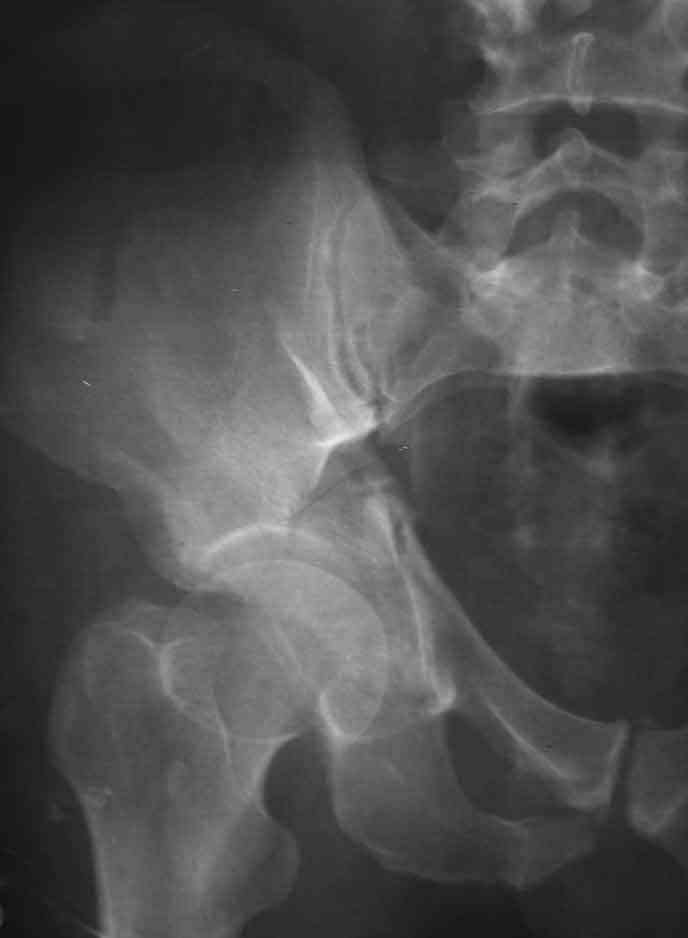

Dear Sir it looks quite difficult classify this fracture because the iliac view is not so clear.

In my opinion it is a column fracture because the obturator foramen is interrupted. There is a fracture of the posterior wall. If we assume the ap view as an iliac view it could be an anterior comun fracture plus posterior wall. It is difficult also to judge the head of the femur.

If you have not a CT scan I think that in order to have a good classification you should obtain a better view of the judet x rays.